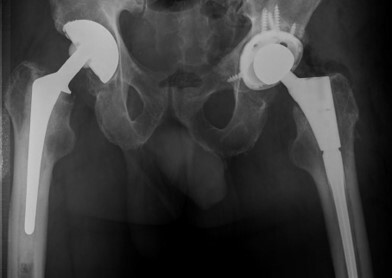

Η θεραπεία για τη περιπροθετική λοίμωξη εξαρτάται από τη σοβαρότητα της κατάστασης και την υποκείμενη αιτία. Οι επιλογές περιλαμβάνουν: